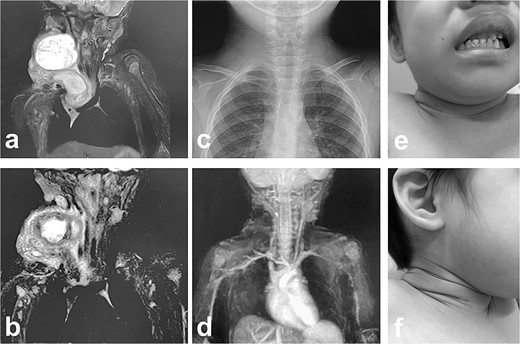

Intra- and post-operative findings from the second operation. (a) The X-ray showed that the tip of the catheter may have moved within the cyst, causing the catheter tip to penetrate the cyst. (b) The X-ray showed the rounded tip of the catheter fixed with threads. (c) Intraoperative findings showed that the tip of the catheter penetrated the cyst wall (black arrow). (d) There were cyst walls with a septum on the mediastinal side of the cyst and when incised old bleeding was noted. The walls were opened as much as possible. (e) The tip of the catheter was rounded and fixed with threads. The catheter was then placed back into the cyst and the wound was closed.

MRI findings after removal of the Denver shunt catheter. (a) MRI findings showed two different areas of intensity in the neck region and the mediastinal region where the Denver shunt was inserted. (b) MRI findings 2 months postoperatively showed that the mediastinal lesion was smaller with near-complete regression. (c) X-ray showed no tumor shadow and no compression of the trachea by the lymphangioma. (d) MRA showed disappearance of the lymphangioma. (e) and (f) Right cervical swelling did not become evident, even when crying (e: crying, f: smiling).